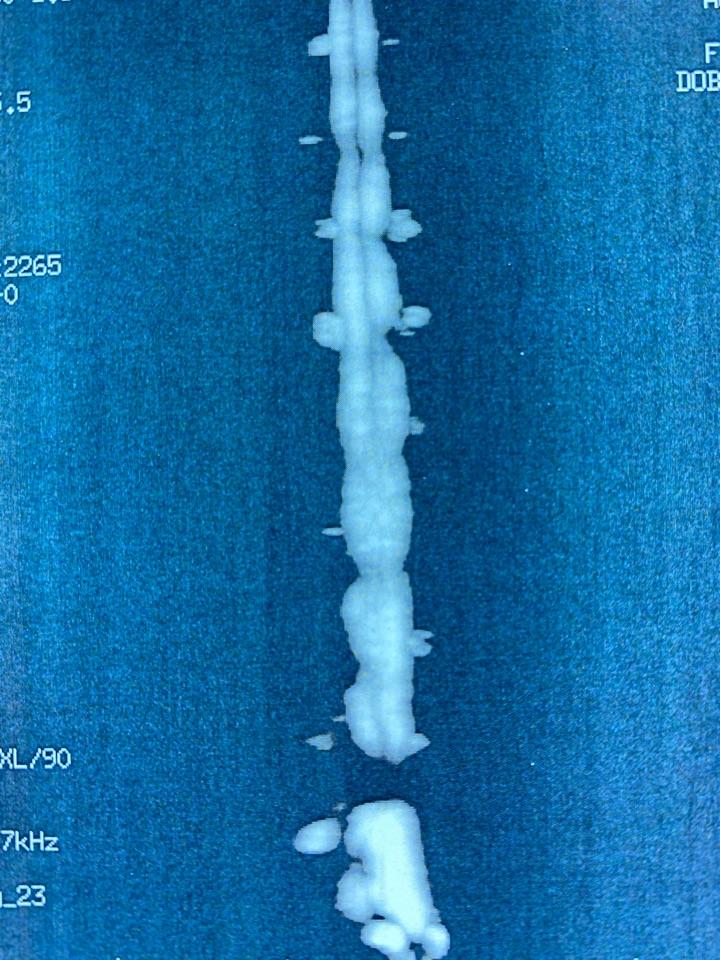

椎管造影示:腰4-5层面完全梗阻